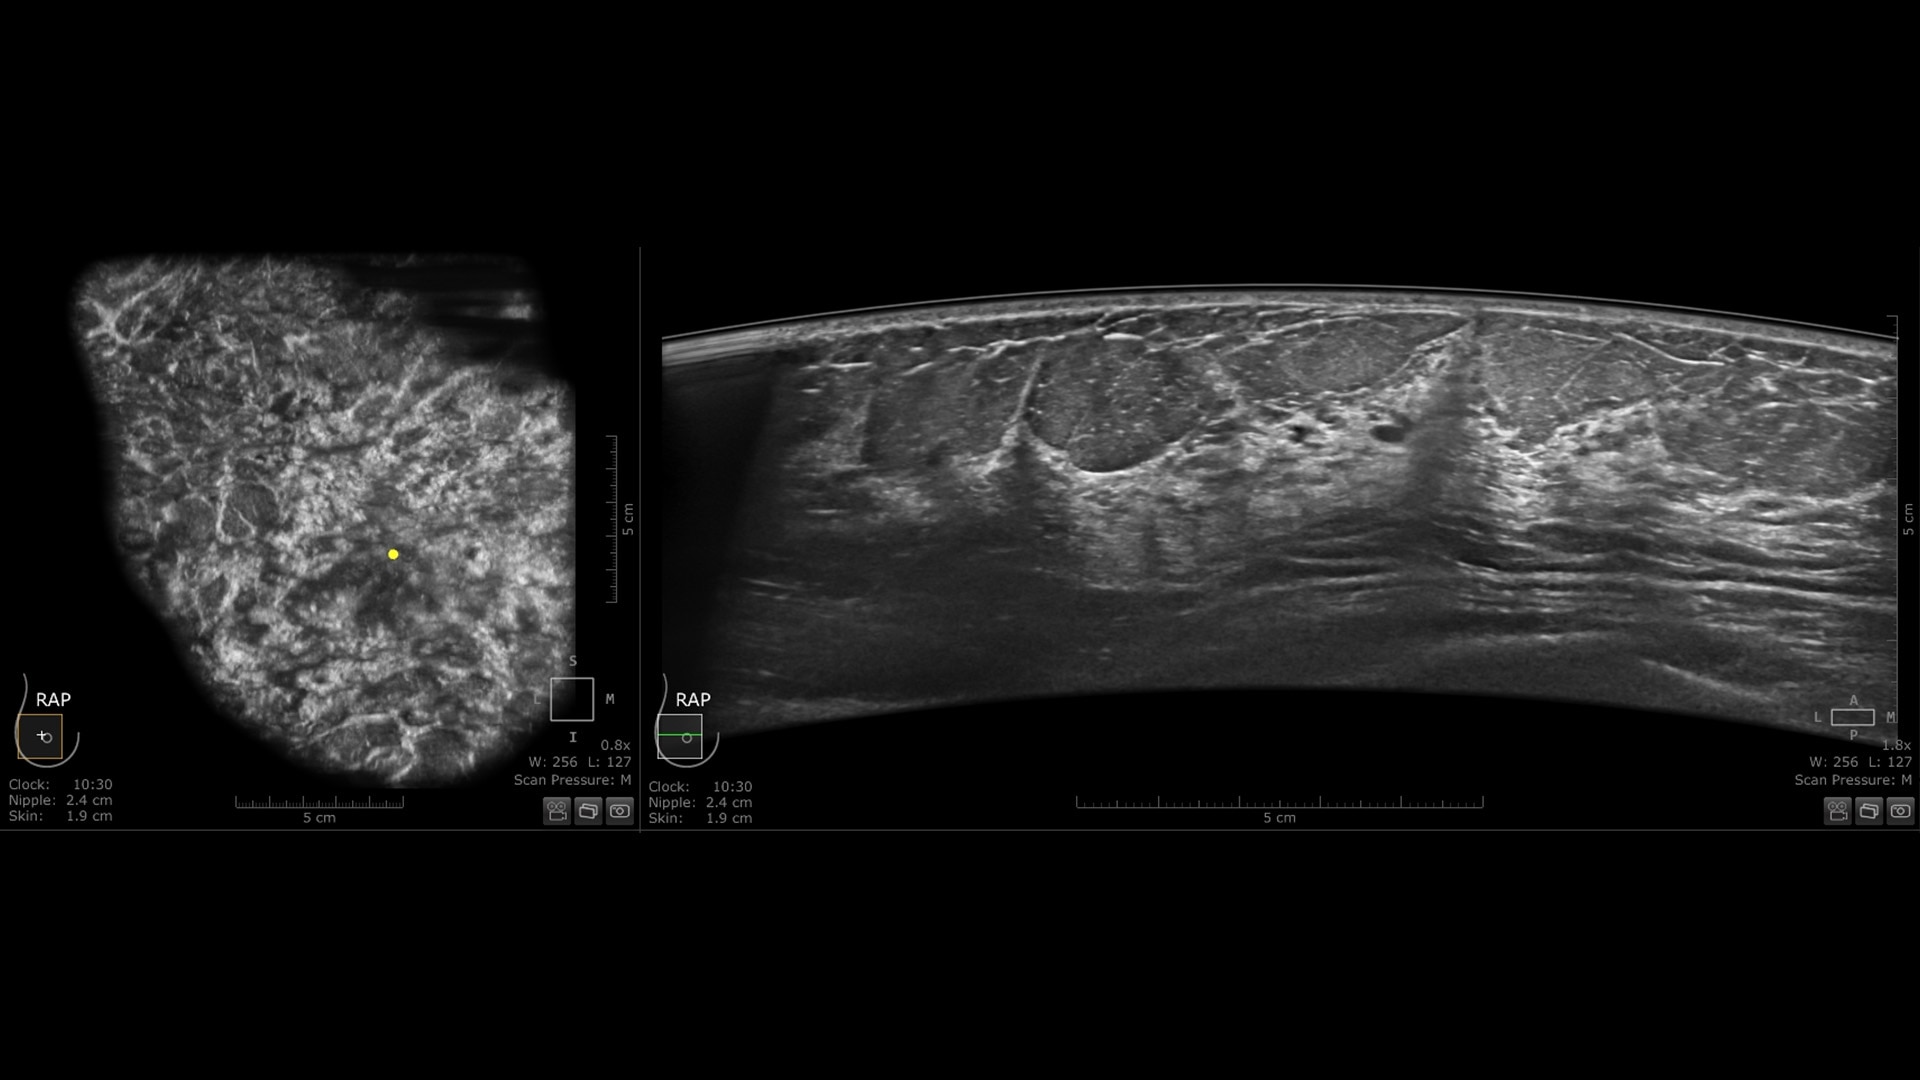

The Invenia ABUS Premium is designed for high patient throughput and extraordinary image quality to provide a great level of confidence. With its innovative design, it’s easy to use, reproducible, user-independent, standardized and allows reading anywhere.

The novel Reverse Curve™ transducer is designed for enhanced performance

Its gentle 15.3 cm shape follows the breast's natural contour, enhancing patient comfort* and ensuring full contact for comprehensive coverage. The improved image quality* increases diagnostic confidence for reading ABUS exams.

Excellent image quality and 40% faster scan speed

• cSound Imageformer, software-based processing, produces exquisite, reproducible images by leveraging automatic focus at every pixel.

• Fast Scan increases scan speed by 40%*, fostering improved efficiency and patient throughput.